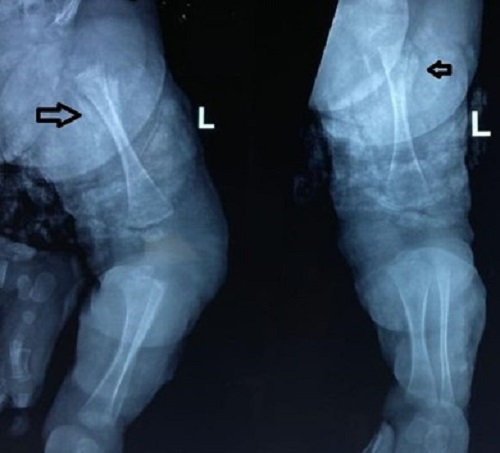

Figure 3

(a) Extensive diaphyseal osteomyelitis in the upper end of the right tibia and (b) Rarefaction distal end of the left femur.

A 15-day-old male baby was admitted with swelling around the right shoulder joint, right knee, and right index finger for 3 days and associated fever for 2 days. There was no history of decreased movements at the shoulder and knee joints. The baby had term gestation and had respiratory distress at birth, kept in the NICU for 5 days on oxygen support—no h/o umbilical catheterization. On examination, the baby had tender swelling with fluctuation around the right shoulder joint. Blood investigations revealed TLC-27,000/uL (N-70%) and CRP-169 mg/L. X-rays of the right shoulder, right knee, and right index finger were normal. Incision and drainage of shoulder abscess was done. Blood culture and Pus culture both had MRSA growth. Inj. Vancomycin was given for 1 week and the baby was discharged on oral linezolid. But the child again got admitted 5 days after discharge, with swelling above the left knee. X-rays were repeated which revealed left distal femur osteomyelitis and right upper tibia extensive diaphyseal osteomyelitis (Fig. 3). Repeat TLC- 22,000/uL (N-56%) and CRP-70 mg/L. Surgical debridement was done. The baby received 4 weeks of i.v vancomycin and was discharged on an oral antibiotic (Linezolid).